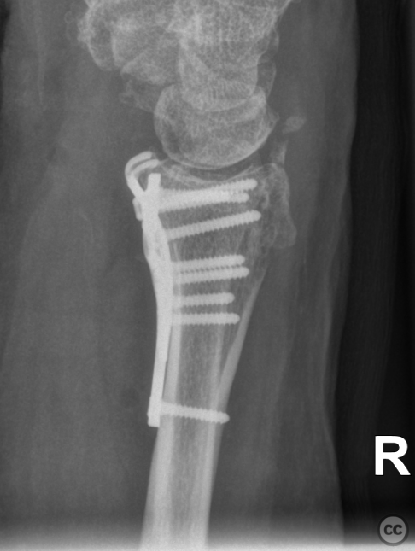

Clinical and radiological findings:  A 72-year-old female sustained a multifragmentary, dorsally displaced distal radius fracture after a fall down stairs. Initial reduction revealed a 180-degree flipped fragment of the volar ulnar articular margin, unreducible by closed means. There was no mention of associated neurovascular compromise or open injury. Radiographs and intraoperative fluoroscopy confirmed the presence of a multifragmentary intra-articular fracture (AO/OTA 23-C3), with a flipped volar ulnar fragment and radial styloid impaction. The distal radioulnar joint alignment was restored postoperatively.

The flipped volar ulnar articular margin fragment was irreducible by closed means due to capsular attachment and required direct open de-rotation and fixation. The impaction and proximal displacement of the radial styloid fragments were challenging due to persistent traction from musculus brachioradialis and scaphoid pressure; ligamentotaxis using Kirschner wire spreader over the scaphoid facilitated reduction. Fragment-specific fixation was necessary: a custom-shaped hook plate for the volar ulnar lip fragment provided stable fixation and prevented dorsal instability, while a separate T-plate addressed the radial styloid. Bicortical locking screws were used to secure both plates, with some screws engaging dorsal fragments from the volar side. Careful adaptation of pronator quadratus over hardware minimized risk of musculus flexor pollicis longus irritation. Additional suture stabilization of radiocarpal ligaments to pronator quadratus provided secondary ligamnetal support.

Orthopaedic implants used:   - 1.0 mm Kirschner wire (provisional fixation) - 1.8 mm Kirschner wire (scaphoid traction) - 2.0 mm Stryker mini fragment T-plate (cut/shaped as hook plate) - 2.4 mm T-plate (radial styloid fixation)